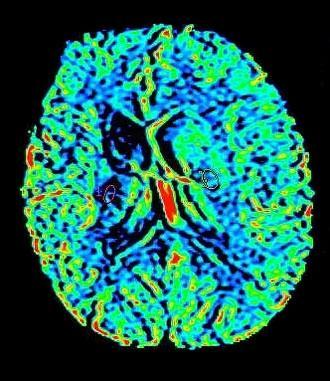

Die Kernspintomographie liefert detailgenaue Schnittbildaufnahmen des menschlichen Körpers ohne Röntgenstrahlen – und das sogar von Blutgefäßen. Bei der MRT werden Sie in einem starken Magnetfeld untersucht. Ähnlich wie bei einem Radio werden UKW-Wellen verwendet. Um dünne Schichtaufnahmen zu erzeugen, benötigen wir zusätzlich schwach wechselnde Magnetfelder, wodurch ein lautes Klopfgeräusch entsteht. Die Signale werden dann von einem sehr leistungsfähigen Computersystem zu Schichtaufnahmen in verschiedenen Ebenen umgewandelt. Die Untersuchung dauert je nach Fragestellung 7 bis 35 Minuten. Während der Messzeit sollten Sie ruhig und entspannt liegen, denn jede Bewegung verursacht Bildstörungen und verlängert die Prozedur.